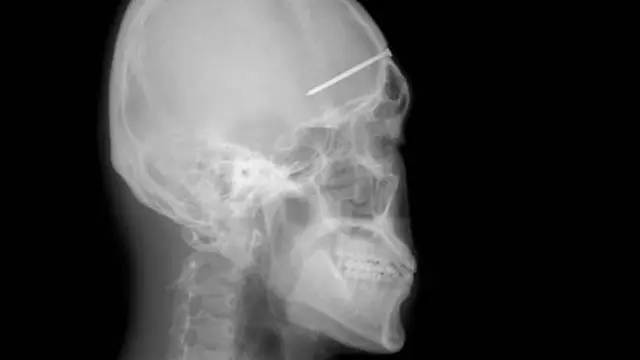

Selamat Dari Tusukan Pisau di Kepala

Ini bukan sulap, ini adalah tragedi yang hampir menewaskan seorang remaja dari China. Ren Hanzhi, remaja 13 tahun tersandung dan terjatuh saat sedang mengupas apel. Kejadian yang sangat cepat ini membuat pisau yang digunakan menembus kepalanya sedalam 20 cm.

Hasil rontgen memang tampak menyeramkan, namun remaja ini selamat. Ajaibnya, pisau tersebut tidak sampai mengenai otak Ren. Bagian pisau tampak hanya menembus bagian samping kepalanya. Dokter berhasil mengeluarkan pisau itu dari kepala sang remaja. Operasi yang sangat berat, karena salah sedikit saja, nyawa Ren bisa melayang.